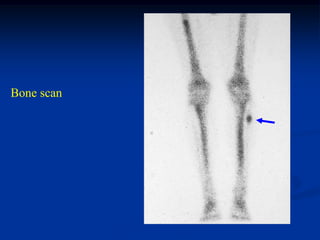

Case #1128.1

57 year male with renal cell CA metastasis to fibular

6 months later without treatment

Bone scan

Sagittal T-2 MRI